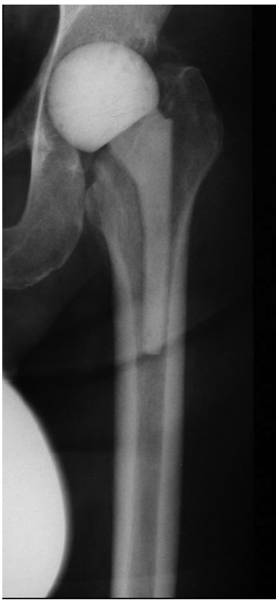

In cases with muscular insufficiency or large acetabular defects, the spacer should not be implanted as a hemiarthroplasty, but rather as a total arthroplasty, consisting of a spacer stem and a cup (Figure 3). This is also of benefit in cases where the spacer head is too small for the acetabulum cavity. Since not every department has molds for production of spacers in different sizes or lengths or the costs for commercially available hip spacers are extremely high, the orthopaedic surgeon is commonly faced with the dilemma: should a larger, hand-molded spacer head be implanted (which, however, has the disadvantage of an inferior articulation due to the uneven head surface and form) or, alternatively, a spacer cup is inserted into the acetabulum. We recommend the second option. This implantation technique also offers the advantage of a prevention of a spacer migration into the pelvis (Figure 4) beside a normal articulation and prevention of any spacer dislocation. Hereby, the cement-cement articulation promotes the emergence of high local antibiotic concentrations due to the continuous friction of the articulating components. Cement debris can be then easily removed at the time of the prosthesis reimplantation via pulsatile lavage and debridement. However, in some cases with a combined muscular insufficiency and large acetabular defects a spacer dislocation might still occur. These cases should be also considered as candidates for a resection arthroplasty.

Figure 3

Articulating hip spacer consisting of a spacer cup and -stem.